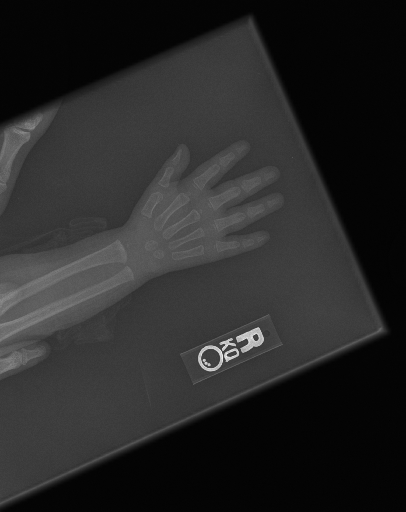

The first step in our pipeline is to detect the X-ray image carrier in the image. To this end, we apply OpenCV’s contour detection using Otsu binarization [14], and retrieve the minimum size bounding box, which does not need to be axis-aligned. This works sufficiently well as long as the majority of the image carrier is within the image (cf. Figure 3). However, the approach might fail for heavily tilted images or those where larger parts of the image carrier reach beyond the image border.

To further improve the detection of hands, and in particular split the images where two hands are depicted on one image, we manually labeled approximately 150 bounding boxes in the images. Using this small dataset, we fine-tune a pre-trained single shot multibox detector (SSD) [12] with MobileNet as taken from TensorFlow. An exemplary results can be seen in Figure 3.